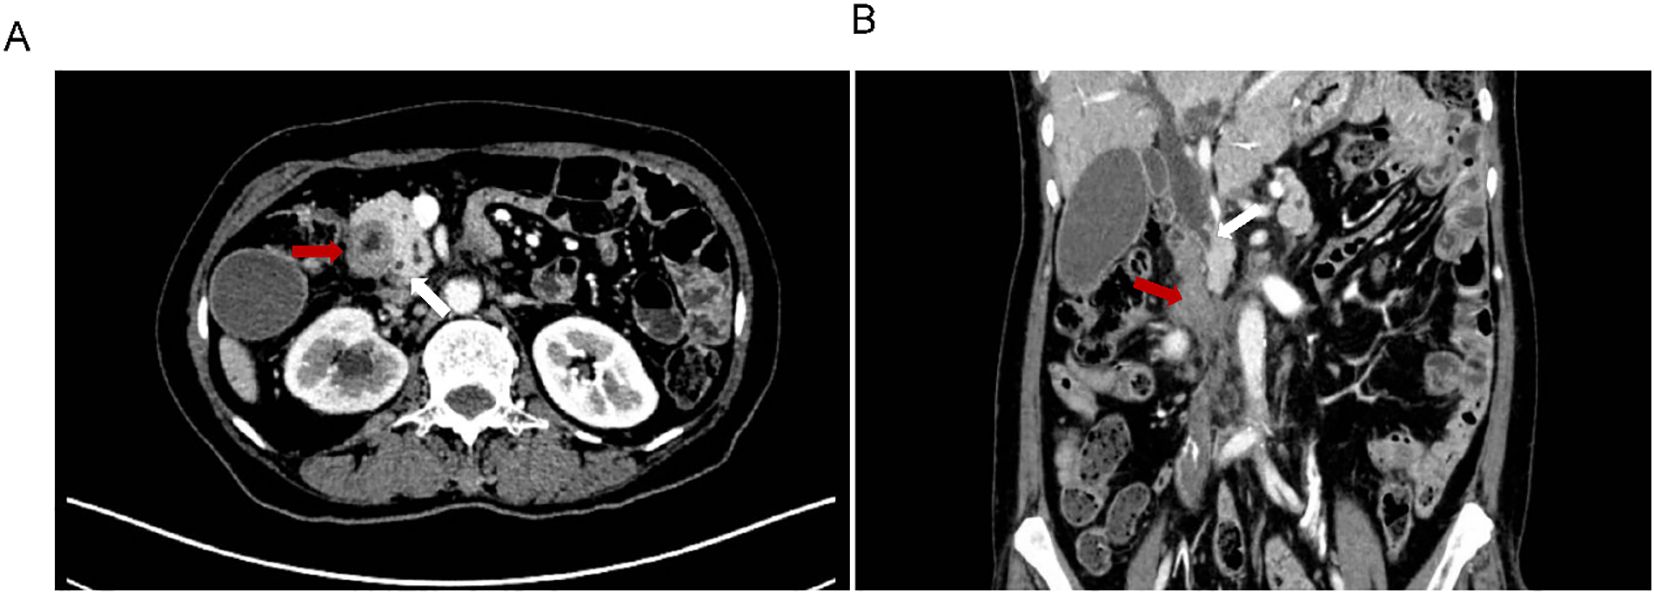

The previous drainage catheter had been in place for an extended period and had become displaced prior to stent placement, necessitating its removal before the procedure. Under real-time ultrasound guidance, a 22G needle was used to puncture the intrahepatic bile duct via a transhepatic route, carefully avoiding the thoracic cavity, hepatic artery, and portal vein. A guidewire (0.035”) was then advanced through a catheter (5F VER 135°) directly into the distal duodenal afferent loop (Figure 3A). Once within the duodenum, the guidewire was manipulated proximally and successfully passed through the obstructed segment. Simultaneous EGD was performed to locate the stricture and retrieve the guidewire using a foreign body forceps. The endoscope was then retracted carefully, pulling the guidewire out through the mouth to create an internal-external access route.

Two-panel medical imaging showing endovascular procedures. Panel A displays a stent graft placed in the abdominal aorta, with a catheter visible. Panel B illustrates a slightly different angle of the stent graft with surrounding contrast-filled arteries.

Figure 3. Procedural imaging. (A) Ultrasound-guided percutaneous transhepatic cholangiography. Intrahepatic bile duct dilatation is observed, and the contrast medium is retained above the previously placed biliary stent. (B) Fluoroscopic image showing the fully expanded duodenal stent in place across the high-grade stricture, with the guidewire and previously placed metal biliary stent in position.

A self-expanding duodenal stent (COOK EVO-22-27-9-D) was advanced over the guidewire under fluoroscopic guidance, with maintained tension on both ends to ensure stability and accurate deployment. After several positional adjustments, the stent was successfully deployed across the stricture (Figure 3B). Fluoroscopic imaging confirmed full expansion of the stent and restoration of luminal patency. The procedure was well tolerated, and the patient reported immediate resolution of obstructive symptoms.